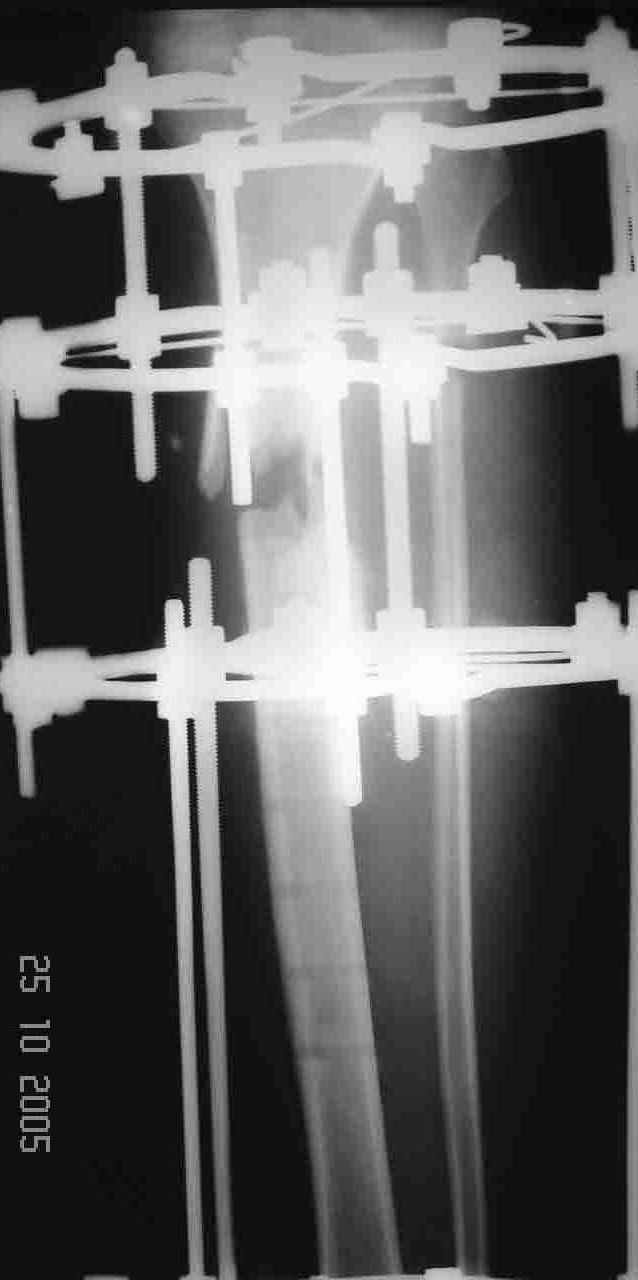

На операции после удаления пластины вывалился промежуточный свободный фрагмент,оставлять его посчитали нецелесообразным. После его удаления вскрыли костномозговой канал, зашили рану и наложили аппарат. После заживления раны концы отломков сблизили. Возможно, всё это же можно было бы сделать одномоментно и на стержне. Но как то мы не решились забить гвоздь при наличии большой раны и костного дефекта. Сейчас 2 недели после операции, больной ходит при помощи костылей с одинаковой нагрузкой на обе ноги. Укорочение в итоге 1,5 см. Обязуюсь показать снимки через пару месяцев.

Причина перелома - на мой взгляд - неадекватная репозиция. Сегмент удлинен, об этом говорит диастаз между отломками малоберцовой кости. Отсюда и впечатление "дефекта". Он есть, но вторичен.

Уважаемый Алексей, глядя на Р-граммы левой голени фиксированной пластиной создается впечатление, что имеется дефект б/берцовой кости. Учитывая это при ЧКО необходимо выполнить костную пластику дефекта. В противном случае кость даже после консолидиции останется слабой, что приведет к повторному перелому. Мне кажется, что в данном случае предпочтителен ЗИО б\берцовой кости с рассверливанием костномозгового канала и блокированием, т.к. при ЗИО активизируются процессы регенерации за счет гематомы в области перелома, что приводит к образованию параоссальной костной мозоли. Плюс к этому в кости будет находится прочный фиксатор, который очень редко ломается и не беспокоит пациента.